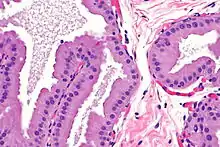

تعد سرطانة الغدد المفترزة نوعًا نادرًا جدًا من سرطان الثدي عند النساء. يتراوح معدل الإصابة من 0.5 إلى 4٪ تقريباً. من الناحية الخلوية تكون خلايا سرطان الغدد المفترزة كبيرة نسبيًا، وحبيبية، ولها سيتوبلازم يوزيني بارز.[3] عندما يتم اختبار سرطان الغدد المفترزة على أنه "ثلاثي السلبية" ، فهذا يعني أن خلايا المريض لا يمكنها التعبير عن مستقبلات هرمون الاستروجين أو مستقبلات البروجسترون أو مستقبلات HER2/neu.[4]